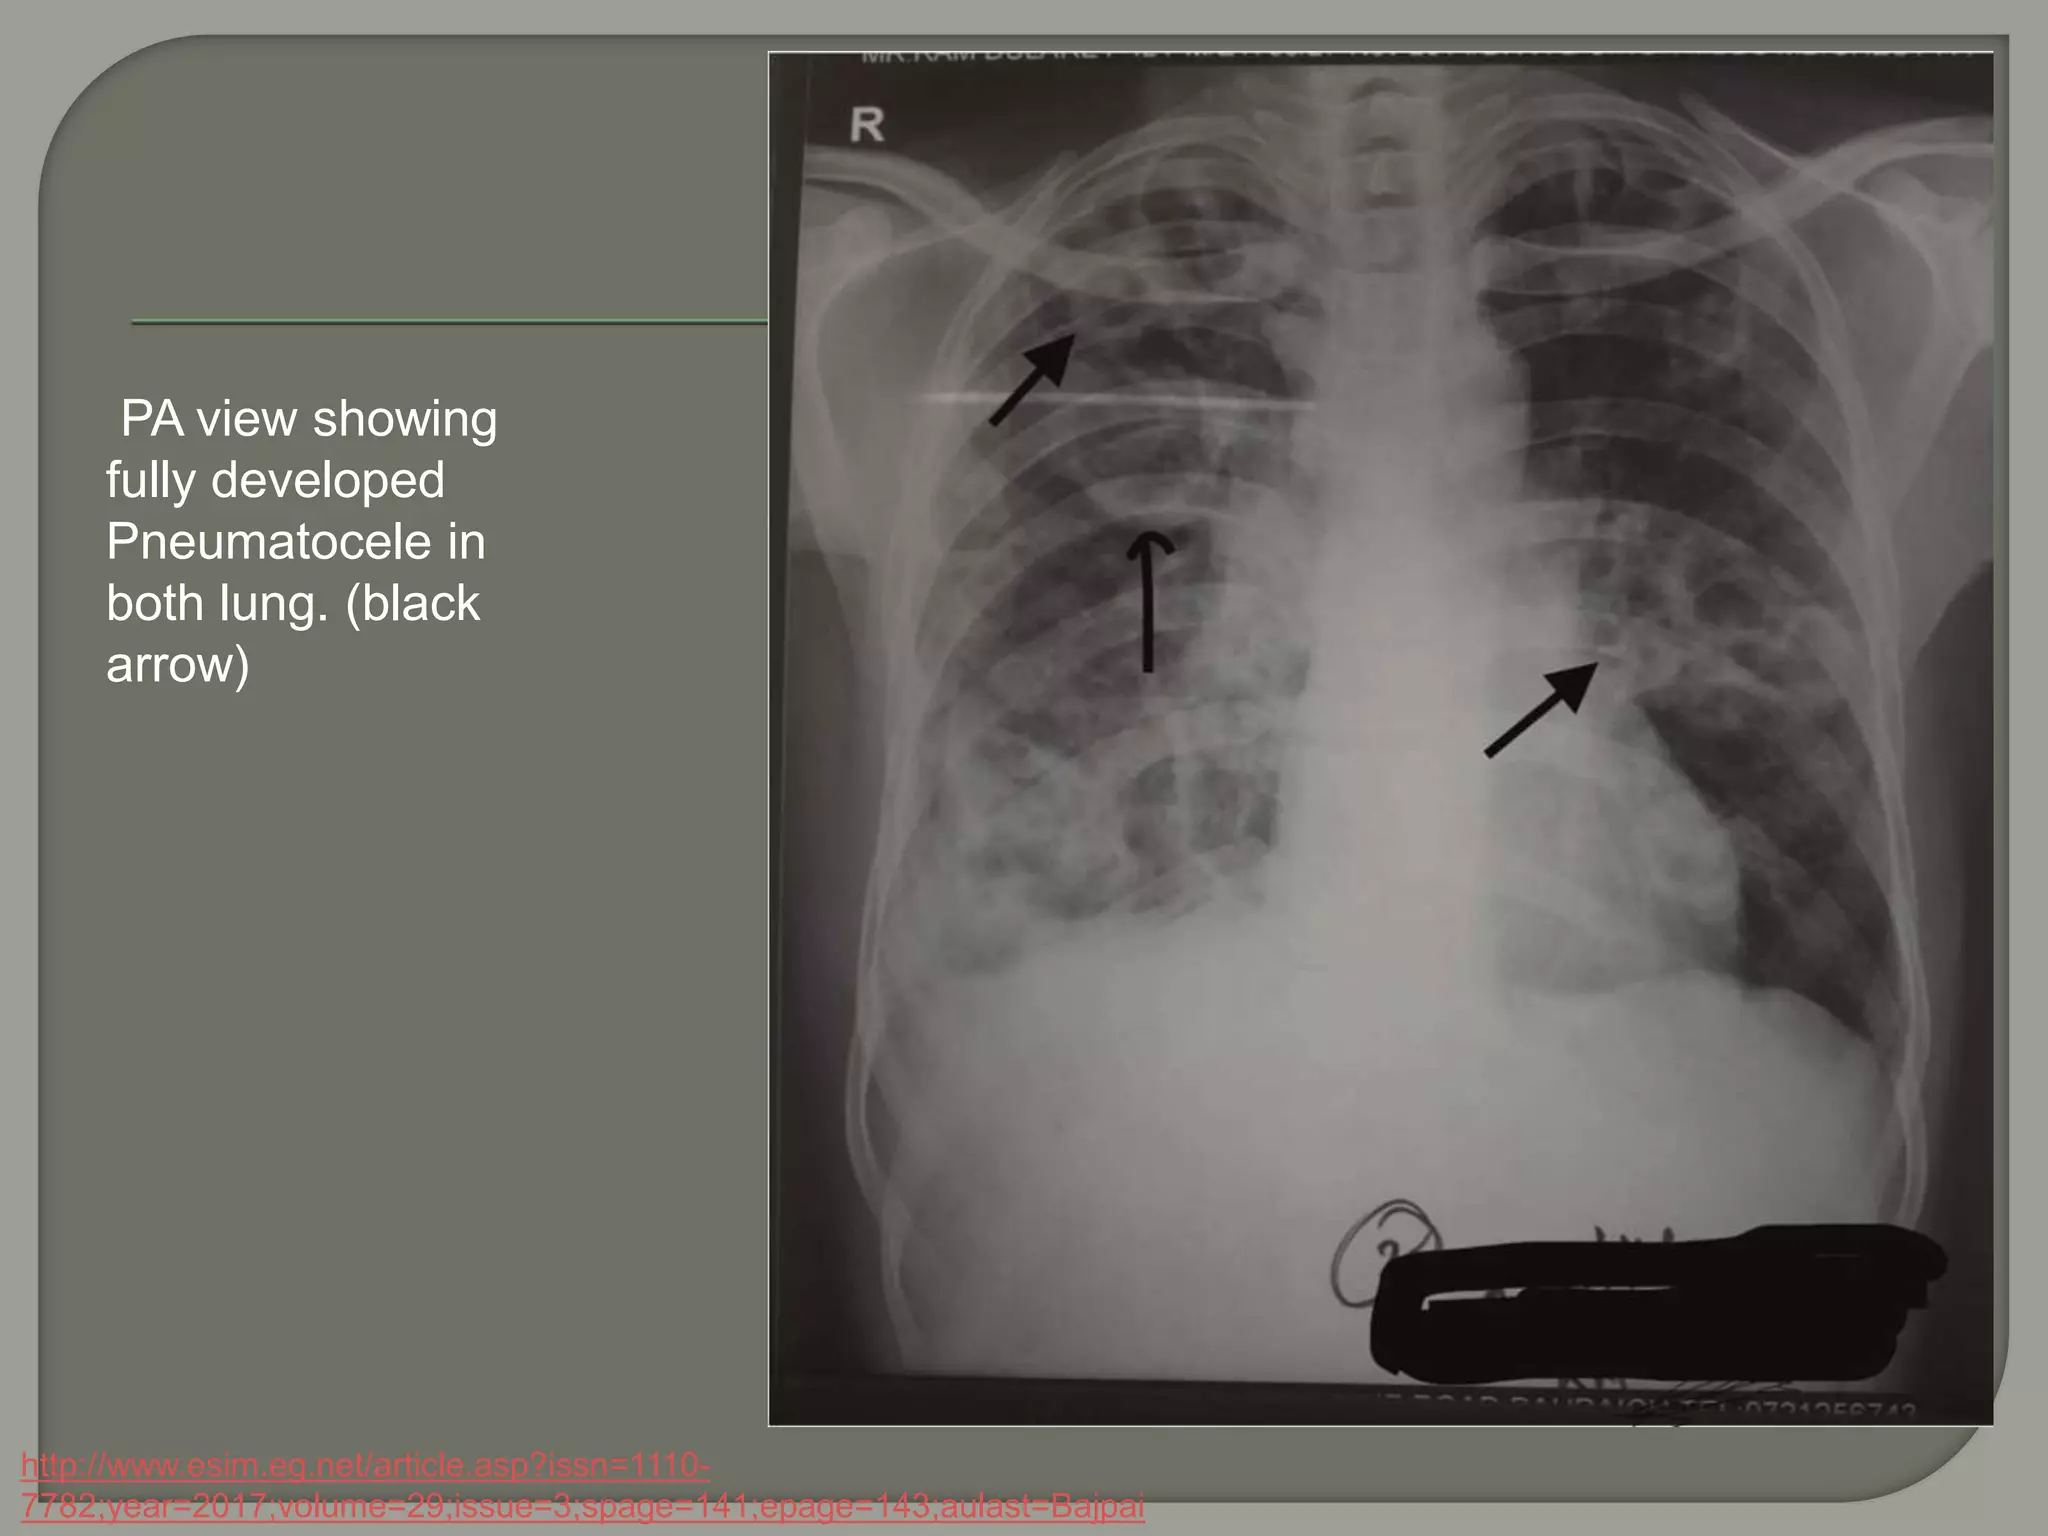

PA view showing

fully developed

Pneumatocele in

both lung. (black

arrow)

http://www.esim.eg.net/article.asp?issn=1110-

7782;year=2017;volume=29;issue=3;spage=141;epage=143;aulast=Bajpai

 Pneumatocoele

Thin-walled (< 1mm), gas-filled space in

the lung developing in association with

acute pneumonia(such as staph) and

trauma .frequently transient